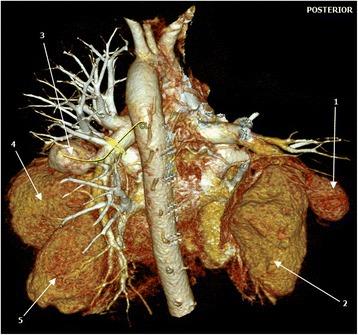

A 24-year-old man, a nursing student of African descent, was referred to us from an up-country regional hospital with a 4-week history of recurrent episodes of breathlessness, awareness of heartbeats and coughing blood 3 weeks after completing a 6-month course of anti-tuberculosis drugs. A physical examination revealed conjuctival and palmar pallor but there were no stigmata of connective tissue disorders, systemic vasculitides or congenital heart disease. An examination of the cardiovascular system revealed accentuated second heart sound (S) with early diastolic (grade 1/6) and holosystolic (grade 2/6) murmurs at the pulmonic and tricuspid areas respectively. Blood tests showed iron deficiency anemia, prolonged bleeding time, and mild hyponatremia. A chest radiograph revealed bilateral ovoid-shaped perihilar opacities while a computed tomography scan showed bilateral multiple pulmonary artery pseudoaneurysms with surrounding hematoma together with adjacent cystic changes, consolidations, and tree-in-bud appearance. Our patient refused to undergo surgery and died of aneurismal rupture after 9 days of hospitalization.

一名24岁的男性,是一名非洲裔护理专业学生,在完成6个月抗结核药物疗程3周后,因反复出现气短、心悸和咯血4周,被一家偏远地区医院转诊至我院。体格检查发现结膜和手掌苍白,但无结缔组织病、系统性血管炎或先天性心脏病的体征。心血管系统检查发现第二心音亢进(S),分别在肺动脉和三尖瓣区有舒张早期(1/6级)和全收缩期(2/6级)杂音。血液检查显示缺铁性贫血、出血时间延长和轻度低钠血症。胸部X线片显示双侧肺门周围椭圆形阴影,而计算机断层扫描显示双侧多发肺动脉假性动脉瘤伴周围血肿,以及相邻的囊性改变、实变和树芽征。我们的患者拒绝接受手术,住院9天后死于动脉瘤破裂。